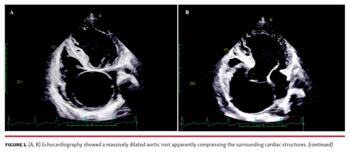

A 25-year-old man came to our clinic with complaints of exertional palpitations and dyspnea. He had skeletal features suggestive of Marfan’s syndrome, including increased arm span, wrist and thumb signs, kyphoscoliosis, and pectus carinatum. Examination revealed a wide pulse pressure, cardiomegaly, and early diastolic murmur of aortic regurgitation. The echocardiogram was peculiar in showing a massively dilated aortic root, apparently compressing the surrounding cardiac structures (Figures 1A and 1B, Video 1). There was severe aortic regurgitation with a dilated and dysfunctional left ventricle. Contrast-enhanced computed tomography (Figures 1C and 1D) confirmed aneurysmal dilation of the aortic root and the proximal part of the ascending aorta. The largest transverse diameter of the aorta was 14.2 cm at the level of the sinuses of Valsalva. No dissection flap or intramural hematoma was observed. The patient was advised to undergo Bentall procedure for replacement of the aortic valve, aortic root, and ascending aorta. He was, however, lost to follow-up.